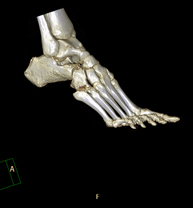

- TC de turmell-peu Exploració radiològica que mitjançant un sistema de raigs X i detectors que giren al voltant del pacient i que reconstrueixen les imatges per ordinador (TC Multidetector), permet l'estudi detallat dels ossos, els músculs i les articulacions del turmell i el peu. Exploració radiològica que mitjançant un sistema de raigs X i detectors que giren al voltant del pacient i que reconstrueixen les imatges per ordinador (TC Multidetector), permet l'estudi detallat dels ossos, els músculs i les articulacions del turmell i el peu.